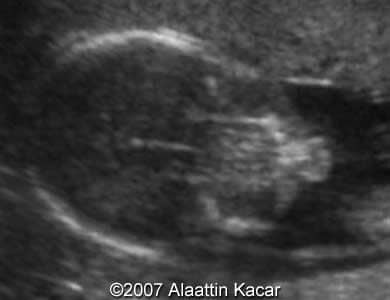

Cleft lip, bilateral Alaattin Kacar, MD Ahmet Celik, MD Merter Keceli,MD. Article Published: Jun 21, 2007 Balikesir, Turkey. These are some images demonstrating bilateral cleft lip of the fetus obtained at 17 weeks of pregnancy. Images 1, 2: Axial images at the level of the upper lip showing bilateral clefts within the upper lip. Images 1, 2: Parasagittal and sagittal images of the fetal head. Parasagittal image shows cleft at the level of the upper lip. Â Â Discussion Board Start a discussion about this article Add to Favorites Favorite